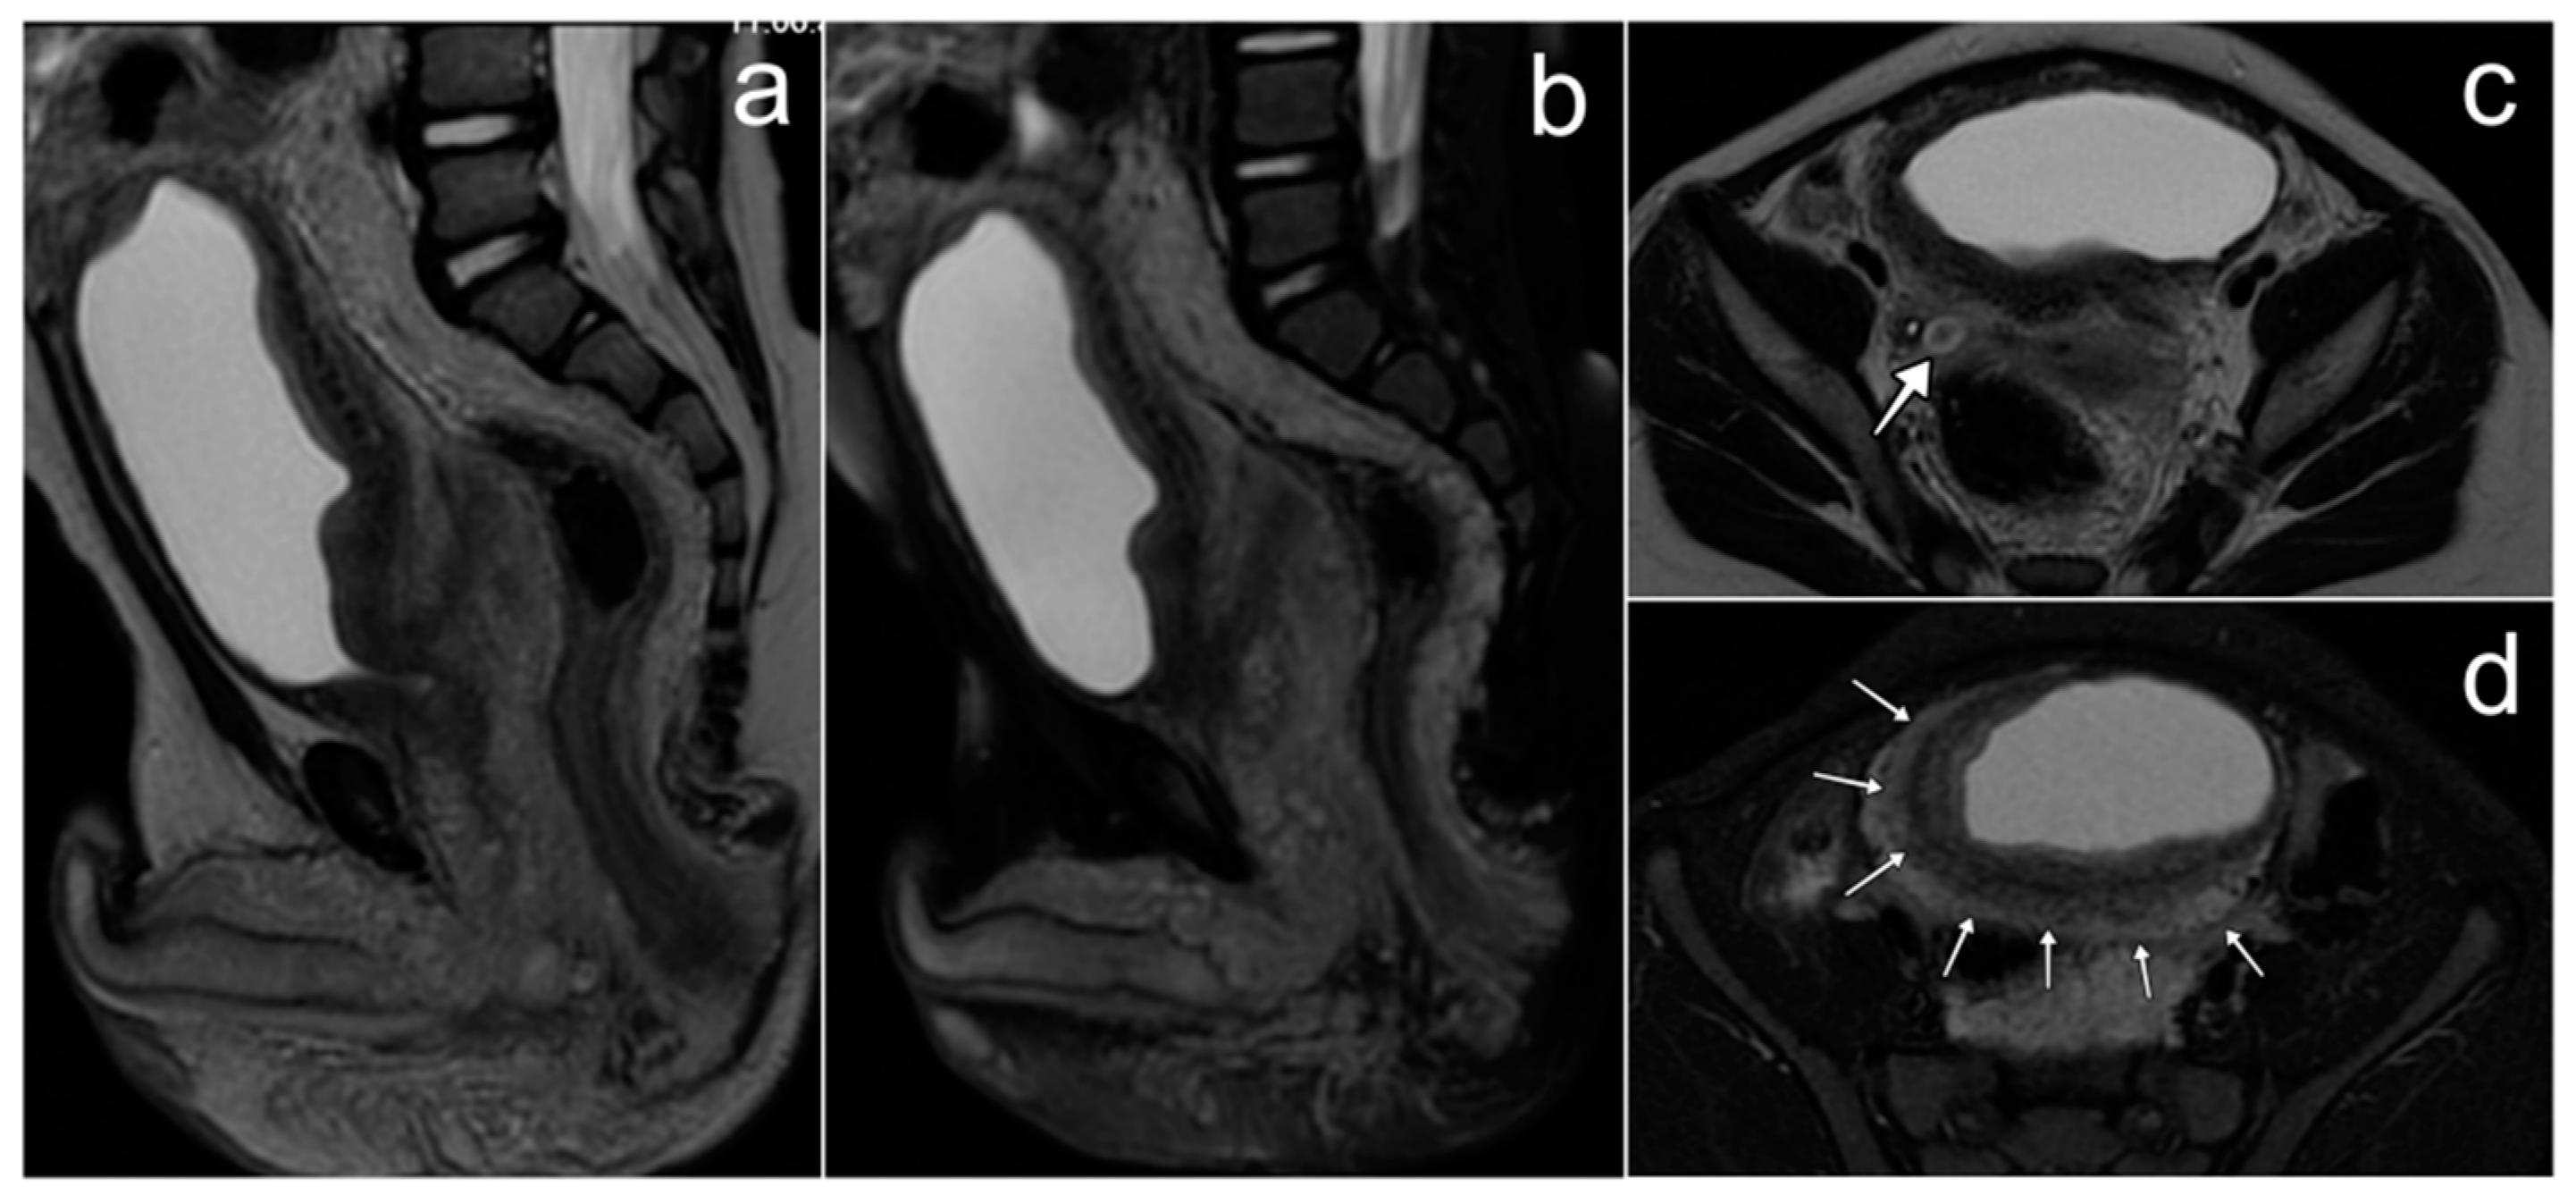

3.5. Primary Ovarian Angiosarcoma with Peritoneal Metastasis

Case Report

| Primary ovarian angiosarcoma | unilateral, sizable, cystic and solid elements in various proportions; hemorrhage; fibrous component | - | non-specific; asymptomatic or neurological symptoms, abdominal pain and distension |